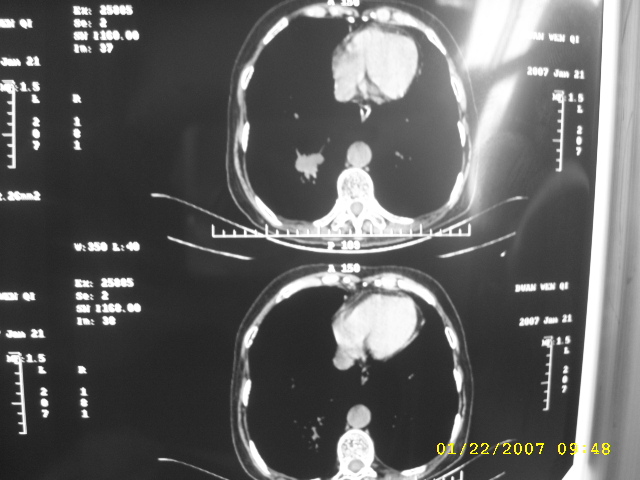

女,75.胸痛。

07.01.21.

明显的不规则形肿块,分叶、短毛刺、胸膜刺激征,血管扭曲征等周围型肺癌的征象明显,应首先考虑周围型肺癌。应与肺多发结核球相鉴别

双侧肺内块状病灶,均见分叶毛刺,左肺见典型胸膜凹陷,双侧双原发癌.

1.双侧周围性肺癌;2.慢支.肺气肿.

支持双原发周围型肺癌;慢支合并肺气肿